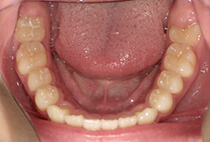

40代女性の患者さま。

グラグラする歯と乱れた歯並びが気になりご来院されました。

「見た目も気になるし、このまま歯が抜けるかも…」そんな不安を抱えていらっしゃいました。

治療は3ステップで進めました。

矯正後は、かぶせ物の治療もあわせて行い、「しっかり噛めて、見た目も自然で美しく」を達成できました。

しっかり噛めるようになったことで頬のコケ間や口元のゆるみが改善され若々しく引き締まった印象になりました。

そして何より、治療終了から15年後も歯ぐき・歯並びともに安定し、健康的で美しいお口元をキープされています。

グラグラする歯と乱れた歯並びが気になる

叢生、重度歯周病

40代女性

矯正治療1年、歯周治療3ヶ月

12回

唇側矯正、審美治療、歯周病治療

矯正:955,900円+毎月調整量:6,050円

歯ぐきの炎症をしっかり改善(歯周病治療)してから、装置セット。

歯並びと噛み合わせを整える(表側矯正・1年間)。

見た目と機能の仕上げ(審美的なかぶせ物)。

治療前

治療後

治療終了から15年後も歯ぐき・歯並びともに安定し、健康的で美しいお口元をキープされています。